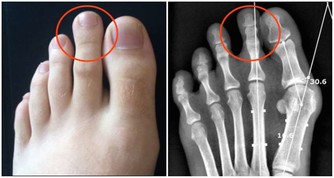

一、腦出血類

長期高血壓、動脈粥樣硬化都可能引發腦出血,造成偏癱、昏迷甚至死亡。

腦出血前兆如下:

1.患者正在做某件事,卻發現自己一側肢體突然失靈了,

例如拿筷子拿不起來,或者拿著的東西突然掉在了地上。

這個症狀很快就會過去,所以容易被忽視。

2.患者突然出現一側嘴歪和無法眨眼的情況。

3.患者眼前發黑,有想摔倒的感覺。

4.部分出血嚴重的患者,會出現劇烈頭痛。